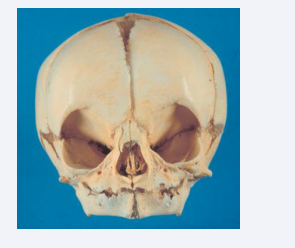

Symphysis Menti

The symphysis menti is still an open symphysis at birth [Figure 11]. The exact time for closure is not known, but probably about 1year of age [17].

Figure 11 Frontal view of a human cranium from a child aged 0-6 month. In the mandible the symphysis menti is open and the alveolar process  not developed.

Figure 11: Frontal view of a human cranium from a child aged 0-6 month. In the mandible the symphysis menti is open and the alveolar process not developed.